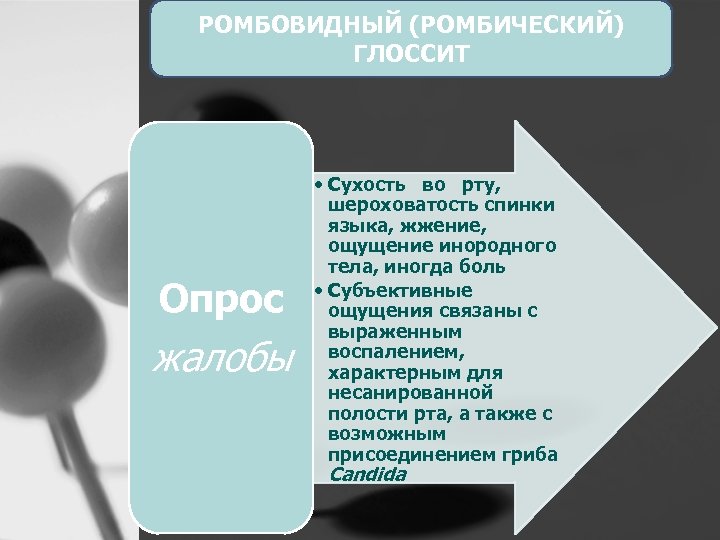

РОМБОВИДНЫЙ (РОМБИЧЕСКИЙ) ГЛОССИТ Опрос жалобы • Сухость во рту, шероховатость спинки языка, жжение, ощущение инородного тела, иногда боль • Субъективные ощущения связаны с выраженным воспалением, характерным для несанированной полости рта, а также с возможным присоединением гриба Candida